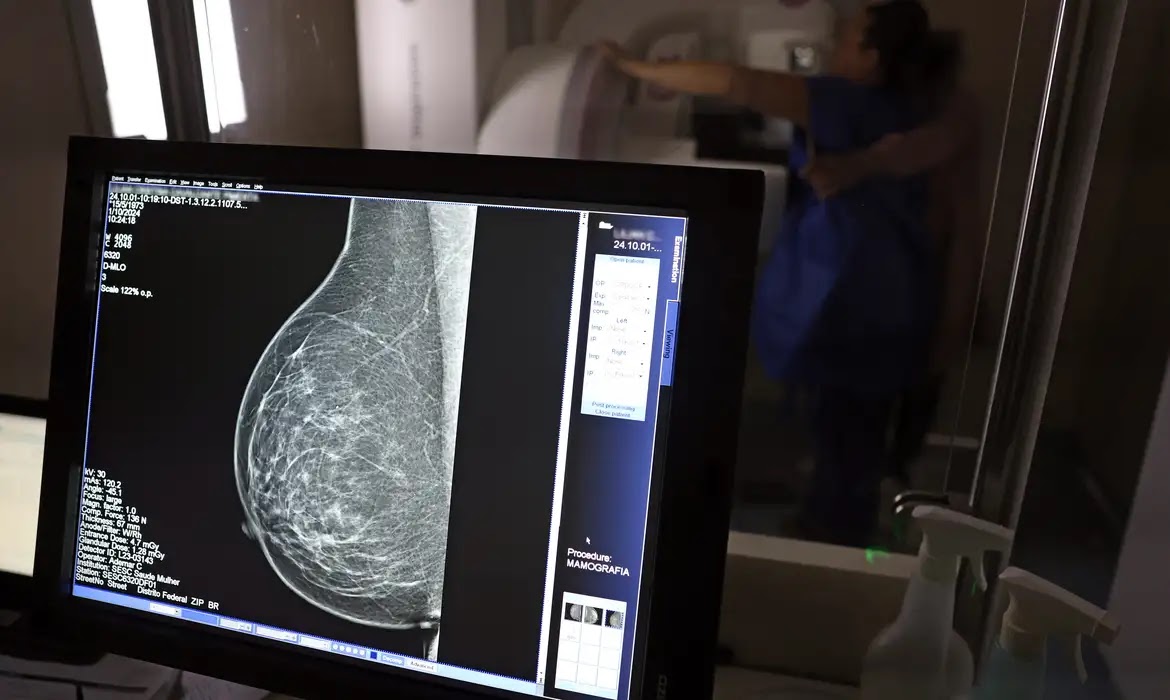

Para a entidade, os números reforçam a importância de ampliar o rastreamento do câncer de mama por meio da realização de mamografia em mulheres abaixo dos 50 anos e acima dos 70 anos, faixas etárias que não estão incluídas na recomendação padrão de exames preventivos no âmbito do Sistema Único de Saúde (SUS).

O levantamento mostra que, entre janeiro de 2018 e dezembro de 2023, o Brasil registrou mais de 319 mil diagnósticos de câncer de mama, sendo 157,4 mil em mulheres de 50 a 69 anos, faixa etária atualmente recomendada para o rastreamento.

Entre mulheres com idade entre 40 e 49 anos, foram registrados 71.204 casos de câncer de mama, enquanto 19.576 mulheres com idade entre 35 e 39 anos também receberam o diagnóstico da doença. Juntas, ambas as ocorrências representam 33% do total de casos diagnosticados no período.

Já entre mulheres acima de 70 anos, foram identificados 53.240 casos de câncer de mama.